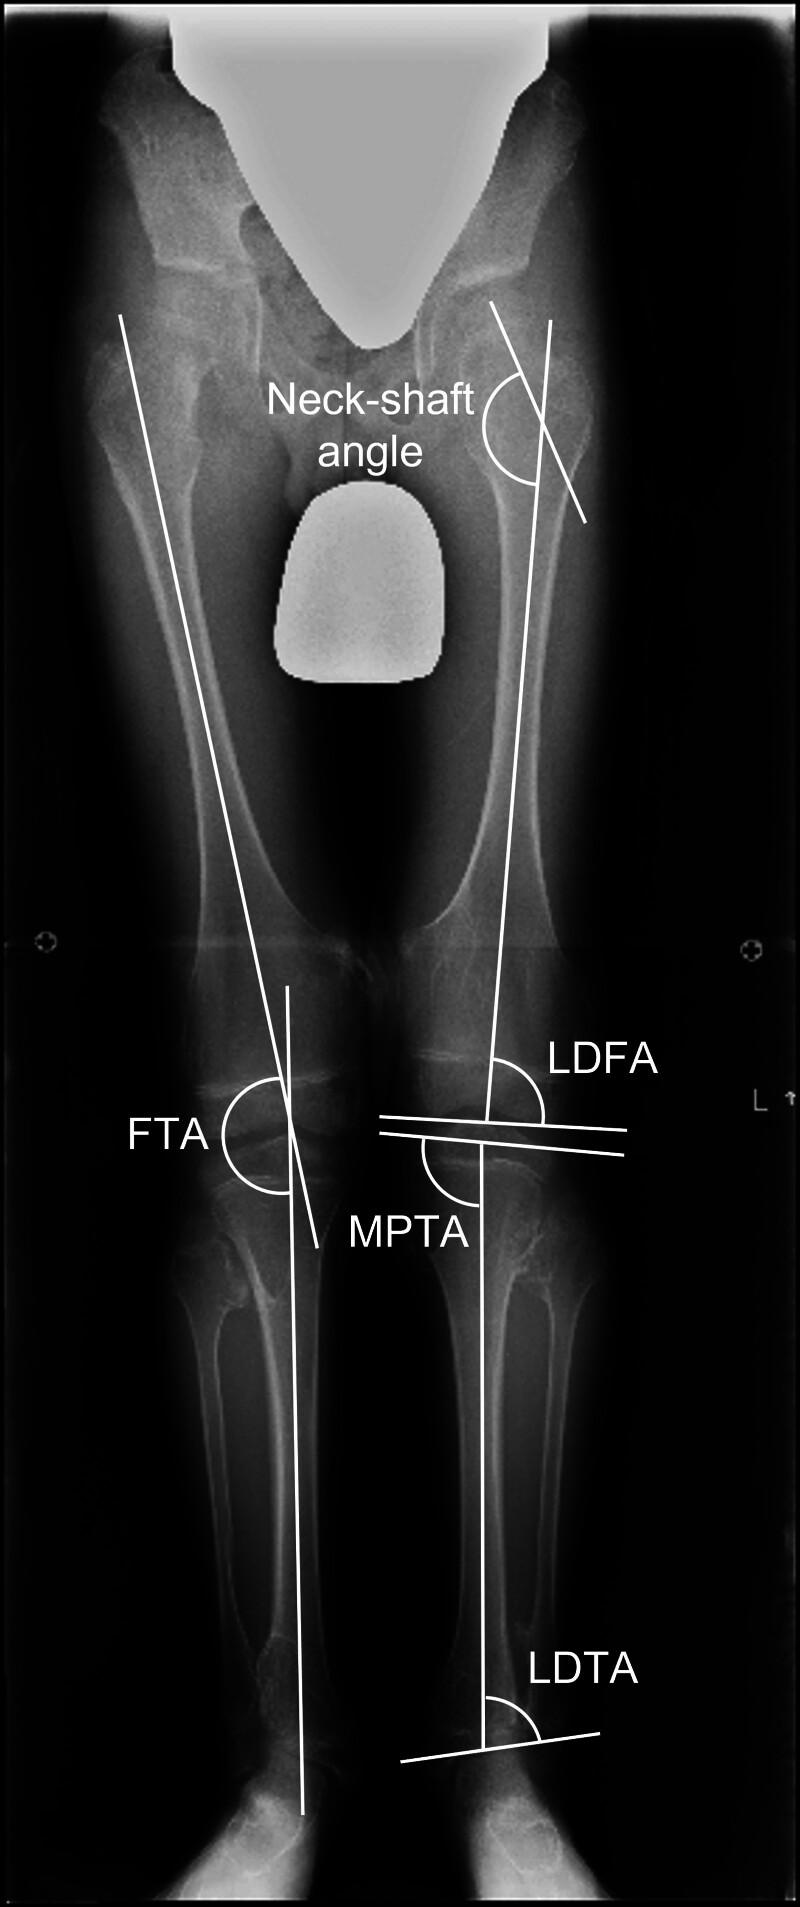

Multiple osteochondromas (MO) occur in approximately 1 in 50,000 people/yr. One in 3 patients with MO will develop valgus knee deformity (VKD), but the predictive factors for VKD are unclear. The purpose of this study was to examine the factors associated with VKD in patients with MO. From January 2003 to December 2018, 64 patients with MO visited the Nagoya University Hospital for the 1st time. Thirty-three patients with 66 limbs were sequentially included in the study after excluding 12 patients with a history of lower extremity surgery, 15 patients whose knee X-rays were unavailable, and 4 patients whose age at the last examination was <7 years. Limbs with femorotibial angle (FTA) ≥ 175° were defined as the normal group (Group N) and limbs with FTA < 175° as the valgus group (Group V), and clinical factors collected retrospectively from the medical records were compared between the 2 groups. The initial and final X-rays were compared in a subgroup analysis of 8 patients whose initial examination was <10 years old and who were followed for more than 5 years. Twenty-four males and 9 females with a median age of 17 years at the last X-rays were included in the study. The mean follow-up period was 43 ± 53 months, and the median FTA was 174.5°. Group N consisted of 32 limbs and Group V consisted of 34 limbs. Multivariate analysis was performed using the 5 factors with P-values <.15 in the univariate analysis of comparison between the 2 groups, and only medial proximal tibial angle showed significant differences (P < .001). In the subgroup analysis, multivariate analysis showed that the femoral neck-shaft angle showed significant differences between the 2 groups at the initial evaluation (P < .001). Our study suggests that medial proximal tibial angle is associated with VKD in patients with MO. Small neck-shaft angle was significantly associated with VKD, even before it became obvious. In order to study how VKD is formed, imaging of the hip and ankle joints and X-rays of the entire lower extremity should be performed in more cases.

多发性骨软骨瘤(MO)的发病率约为每年50000人中1例。每3例MO患者中就有1例会出现膝外翻畸形(VKD),但其预测因素尚不清楚。本研究旨在探讨MO患者中与VKD相关的因素。2003年1月至2018年12月,64例MO患者首次就诊于名古屋大学医院。排除12例有下肢手术史的患者、15例无法获得膝关节X线片的患者以及4例末次检查年龄<7岁的患者后,33例患者的66条肢体被纳入本研究。股骨胫骨角(FTA)≥175°的肢体定义为正常组(N组),FTA<175°的肢体定义为外翻组(V组),并对从病历中回顾性收集的临床因素在两组之间进行比较。在8例初次检查年龄<10岁且随访超过5年的患者亚组分析中,比较了初次和末次X线片。本研究纳入了24例男性和9例女性,末次X线检查时的中位年龄为17岁。平均随访期为43±53个月,中位FTA为174.5°。N组包括32条肢体,V组包括34条肢体。对两组比较的单因素分析中P值<0.15的5个因素进行多因素分析,仅胫骨近端内侧角显示出显著差异(P<0.001)。在亚组分析中,多因素分析显示,初次评估时两组之间的股骨颈干角存在显著差异(P<0.001)。我们的研究表明,胫骨近端内侧角与MO患者的VKD相关。即使在VKD变得明显之前,小的颈干角也与VKD显著相关。为了研究VKD是如何形成的,应在更多病例中对髋关节和踝关节进行影像学检查以及对整个下肢进行X线检查。